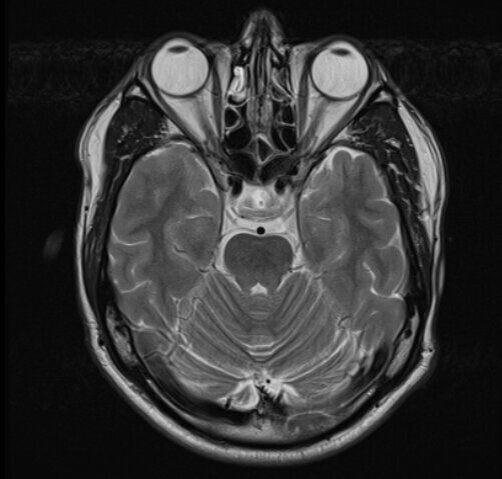

Глазки. 😁

Плоскости изображения:

- Фронтальная.

- Аксиальная.

- Сагиттальная.